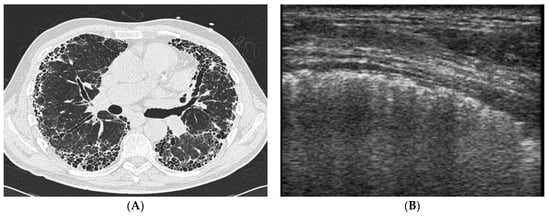

4.2. Does Lung Ultrasound (LUS) Have a Defined Role in pSS-ILD Screening and Follow-Up?

- Vasco, P.G.; Cardenal, G.D.L.; Garrido, I.M.; Pinilla, J.M.L.; Rodríguez, G.F.; Mateo, J.J.N.; Ruiz, D.C. Assessment of interstitial lung disease in Sjögren’s syndrome by lung ultrasound: A pilot study of correlation with high-resolution chest tomography. Intern. Emerg. Med. 2017, 12, 327–331. [Google Scholar] [CrossRef]

- Ferro, F.; Bulleri, A.; Elefante, E.; Tripoli, A.; Mosca, M.; Baldini, C. AB0510 Lung Ultrasound of Pleural Irregularities in Sub-clinical Primary Sjögren’s Syndrome-Lung Involvement: A Single Centre Experience. Ann. Rheum. Dis. 2019, 78 (Suppl. S2), 1718. [Google Scholar] [CrossRef]

- Ferro, F.; Sedie, A.D. The use of ultrasound for assessing interstitial lung involvement in connective tissue diseases. Ann. Rheum. Dis. 2018, 36 (Suppl. S114), 165–170. [Google Scholar]